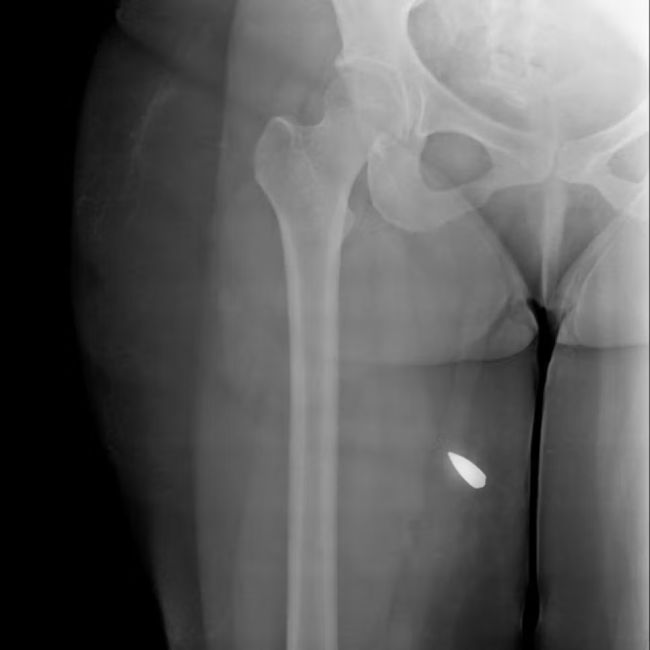

در ۹ بیمار، گلوله‌های کالیبر بالا همچنان در بدن باقی مانده و در تصاویر دیده می‌شوند.

در موارد دیگر، مسیر شکستگی استخوان و قطعات فلزی باقی‌مانده نشان می‌دهد احتمالا اصابت گلوله‌های پرسرعت، عامل جراحت بوده‌اند.

کارشناسان این مهمات را از نوع «تمام‌فلزی» معرفی کرده‌اند؛ گلوله‌هایی که معمولا با سلاح‌هایی مانند ای‌کی-۴۷ (AK-47) شلیک می‌شوند و شکل خود را حفظ می‌کنند.

یکی از کارشناسان به گاردین گفته است: «این‌ها سلاح‌هایی با هدف کشندگی هستند.»